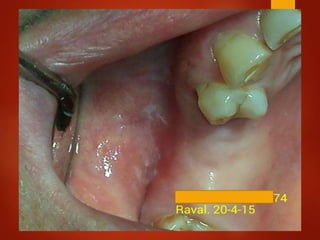

El documento es un registro médico odontológico que muestra las fechas de las visitas de un paciente al centro de salud El Raval, incluyendo exámenes y tratamientos realizados como la extracción de cálculos salivales en abril y mayo de 2012.